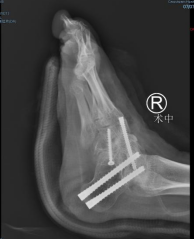

术中

第二天,严谨的术前检查后,俞光荣教授和曹广超主任联合为患者进行了右足三关节融合术,手术顺利完成。国内一流专家和新生代骨干的手术技术严谨而娴熟,矫形到位,术中出血仅20ml。

“这个手术的难点主要是,首先微创跟腱松解,再通过精准的截骨矫形,使关节融合在正常的位置,恢复正常的对合关系。先是距下关节的处理,恢复患者的后足力线,再通过距舟、跟骰的旋转,恢复正常的跖行足结构,由于患者马蹄内翻后侧和内侧的软组织挛缩严重,所以在骨组织矫形后,内侧和后侧的皮肤张力比较大,容易引起皮肤的坏死。我们用了一个切口做三个关节的手术,减少了软组织的剥离,避免了软组织的并发症,保证切口的一期愈合。”